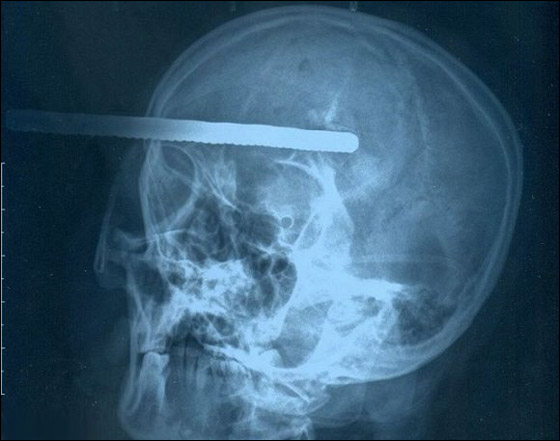

وكشفت صور الأشعة السينية عن أن القضيب اخترق رأس شينغ إلى عمق 8 سنتيمترات، على مقربة من جذع دماغها. وتمكن الجراحون من إزالة القضيب وقالوا ان حالة شينغ خطيرة ولكنها لا تهدد حياتها.

وخضعت شينغ فينغهوا، وهي من مدينة انكينغ باقليم آنهوي، وتبلغ من العمر 48 عاما، لجراحة طارئة لإزالة القضيب الذي اخترق جمجمتها إلى عمق 8 سنتيمترات، وكاد أن يصل إلى جذع دماغها. وكانت شينغ تعمل في موقع البناء عندما سقطت قطعة سيخ طولها 4 أمتار من سقف مبنى بارتفاع ثلاثة طوابق.